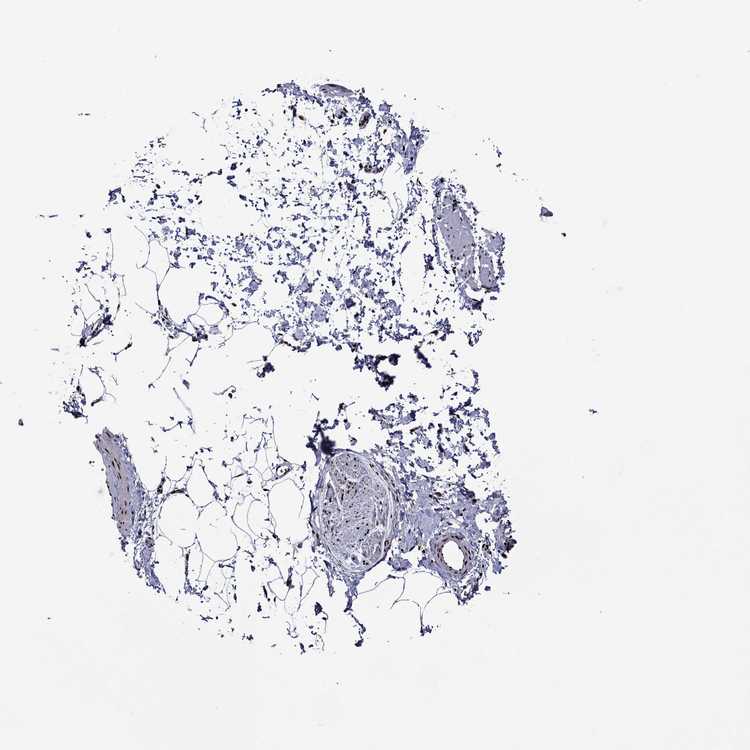

TISSUE PRIMARY DATA SOFT TISSUE Show tissue menu

SOFT TISSUE - Expression summary

SOFT TISSUE 1 - Antibody stainingi

Antibody staining in the annotated cell types in the current human tissue is reported as not detected, low, medium, or high, based on conventional immunohistochemistry profiling in selected tissues. This score is based on the combination of the staining intensity and fraction of stained cells.

Each image is clickable and will lead to virtual microscopy that enables deeper exploration of all samples and also displays staining intensity scores, fraction scores and subcellular localization as well as patient and tissue information for each sample.

Antibody HPA028516Antibody HPA073571

Chondrocytes Low-

Fibroblasts MediumLow

Peripheral nerve LowMedium

SOFT TISSUE 2 - Antibody stainingi

Fibroblasts MediumMedium

Peripheral nerve Not detectedLow